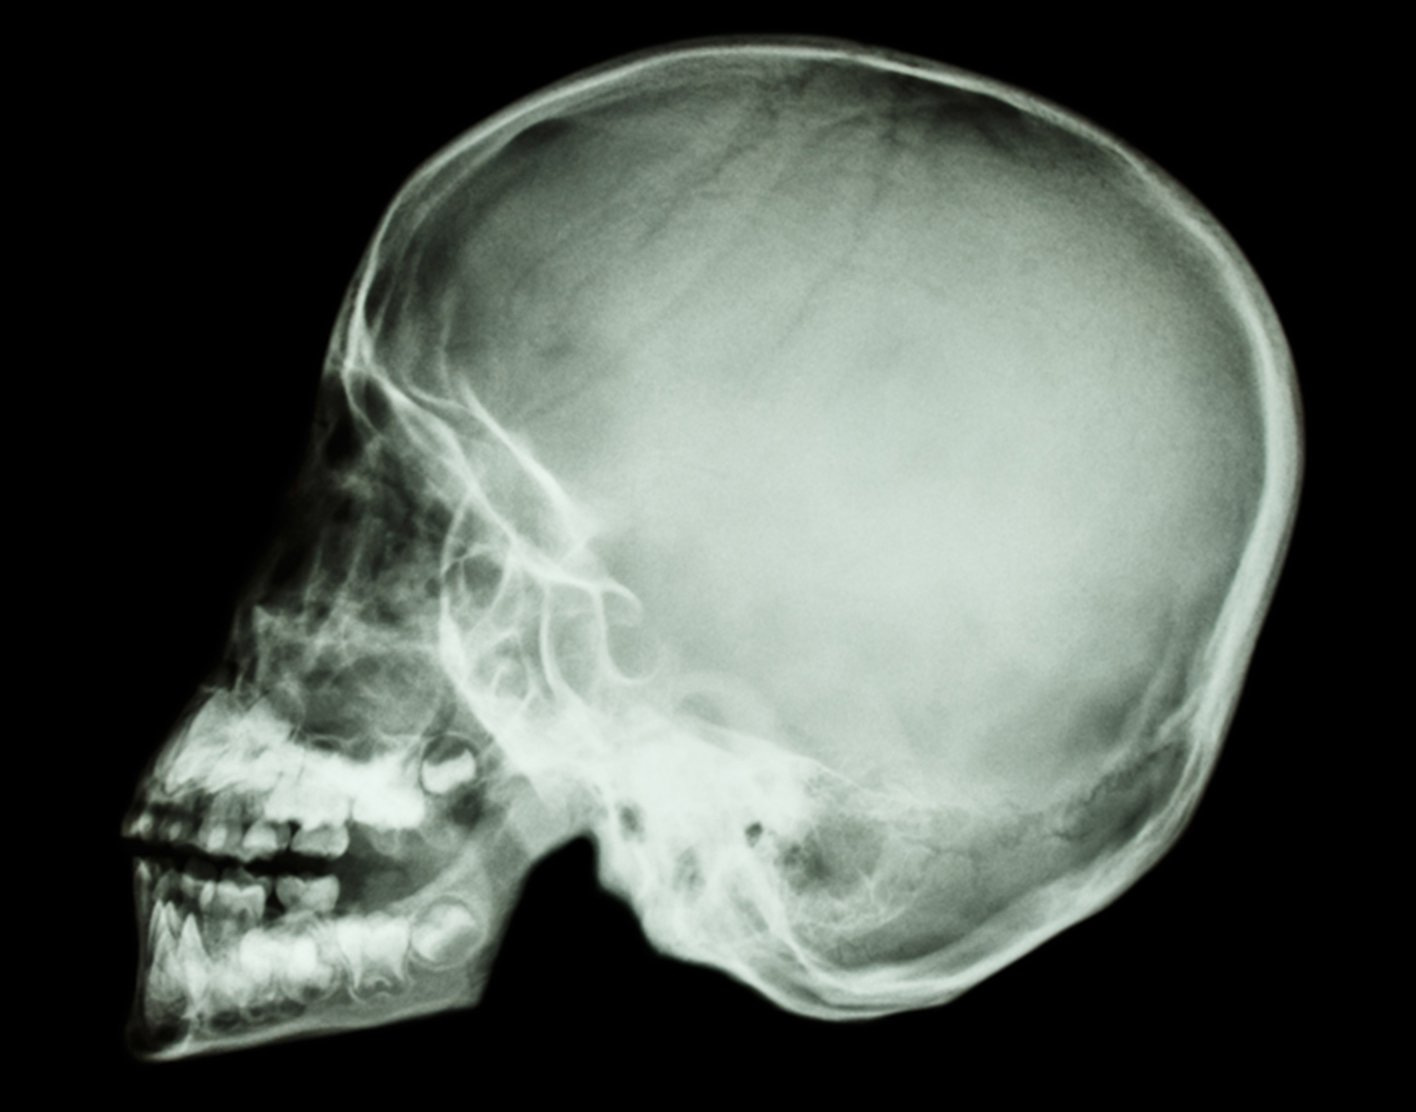

Radiographs, also known as “x-rays”

X-ray: x-rays, or “radiographs” use really high energy photons, that’s the same thing they were talking about when we’re talking about Light. Photons can be Red, photons can be Blue, photons can be really low power radio waves, and they can be really high power x-rays. When you take a really high power x-ray, which is a photon vibrating very very fast, with a higher frequency than even ultraviolet light, it can penetrate through the human body. Some of those x-rays will get absorbed on the way through, and others will not.

What determines whether they will go all the way through, and eventually hit a photographic plate on the other side?7 Well, if they hit something dense they’re more likely to be absorbed. If those photons hit something less dense, they cruise through. Bones are dense. Thus they are white on an x-ray because all those x-ray photons got absorbed and didn’t go through to the photographic plate on the back. When passing through the body containing muscle and blood vessels and brains and stuff, less of them get absorbed, and more of those photons hit a photographic plate. Like visual spectrum photons hitting a film negative, it gets darker. When we see x-ray radiographs, we’re looking at negatives, and unlike in photography, we don’t bother to flip the image so that white gets dark to the eye.

But that’s how we get an x-ray machine to make an x-ray picture. And then doctors can look at that and see what’s inside your body. We get the best resolution of bones — they’re the most dense.